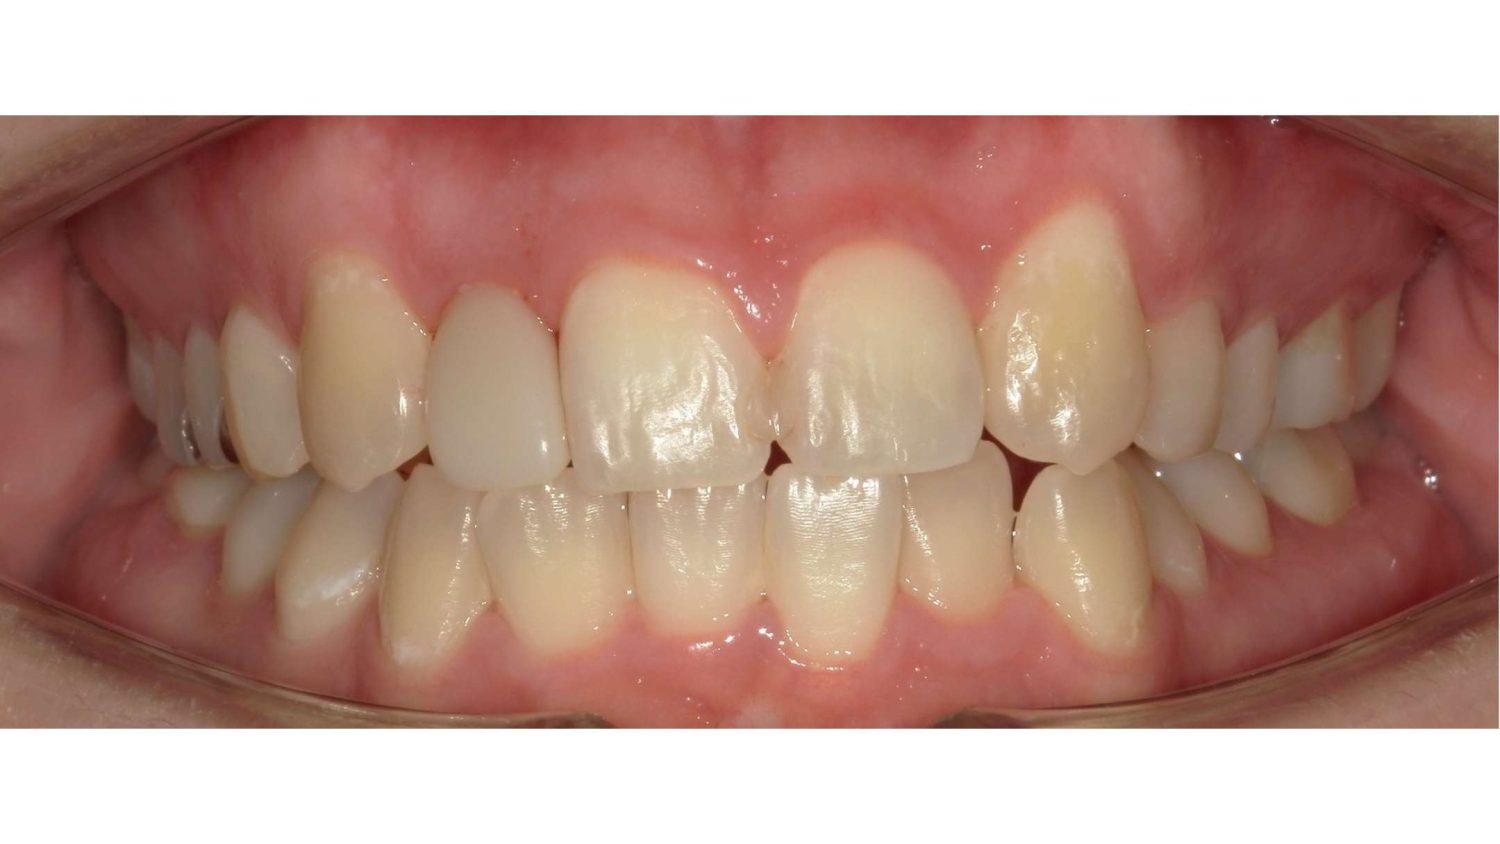

前歯だけの矯正の症例紹介②

Before

After

主訴

上の前歯の横の歯が後ろに引っ込んでいるのでセラミックの被せ物で治したい。

治療内容

ワイヤー矯正で治しました。

治療費

115,500円(税込)(リテーナー込み)

治療期間

4か月

通院回数

5回

想定されたリスク

※当該部位の上下のかみ合わせが反対になっていましたので、上の歯を前に動かすときに引っかかって動かない可能性がありました。

セラミックの被せ物で治すと健全な歯を削ることになってしまうので、患者様と相談し、矯正治療で治すことにしました。